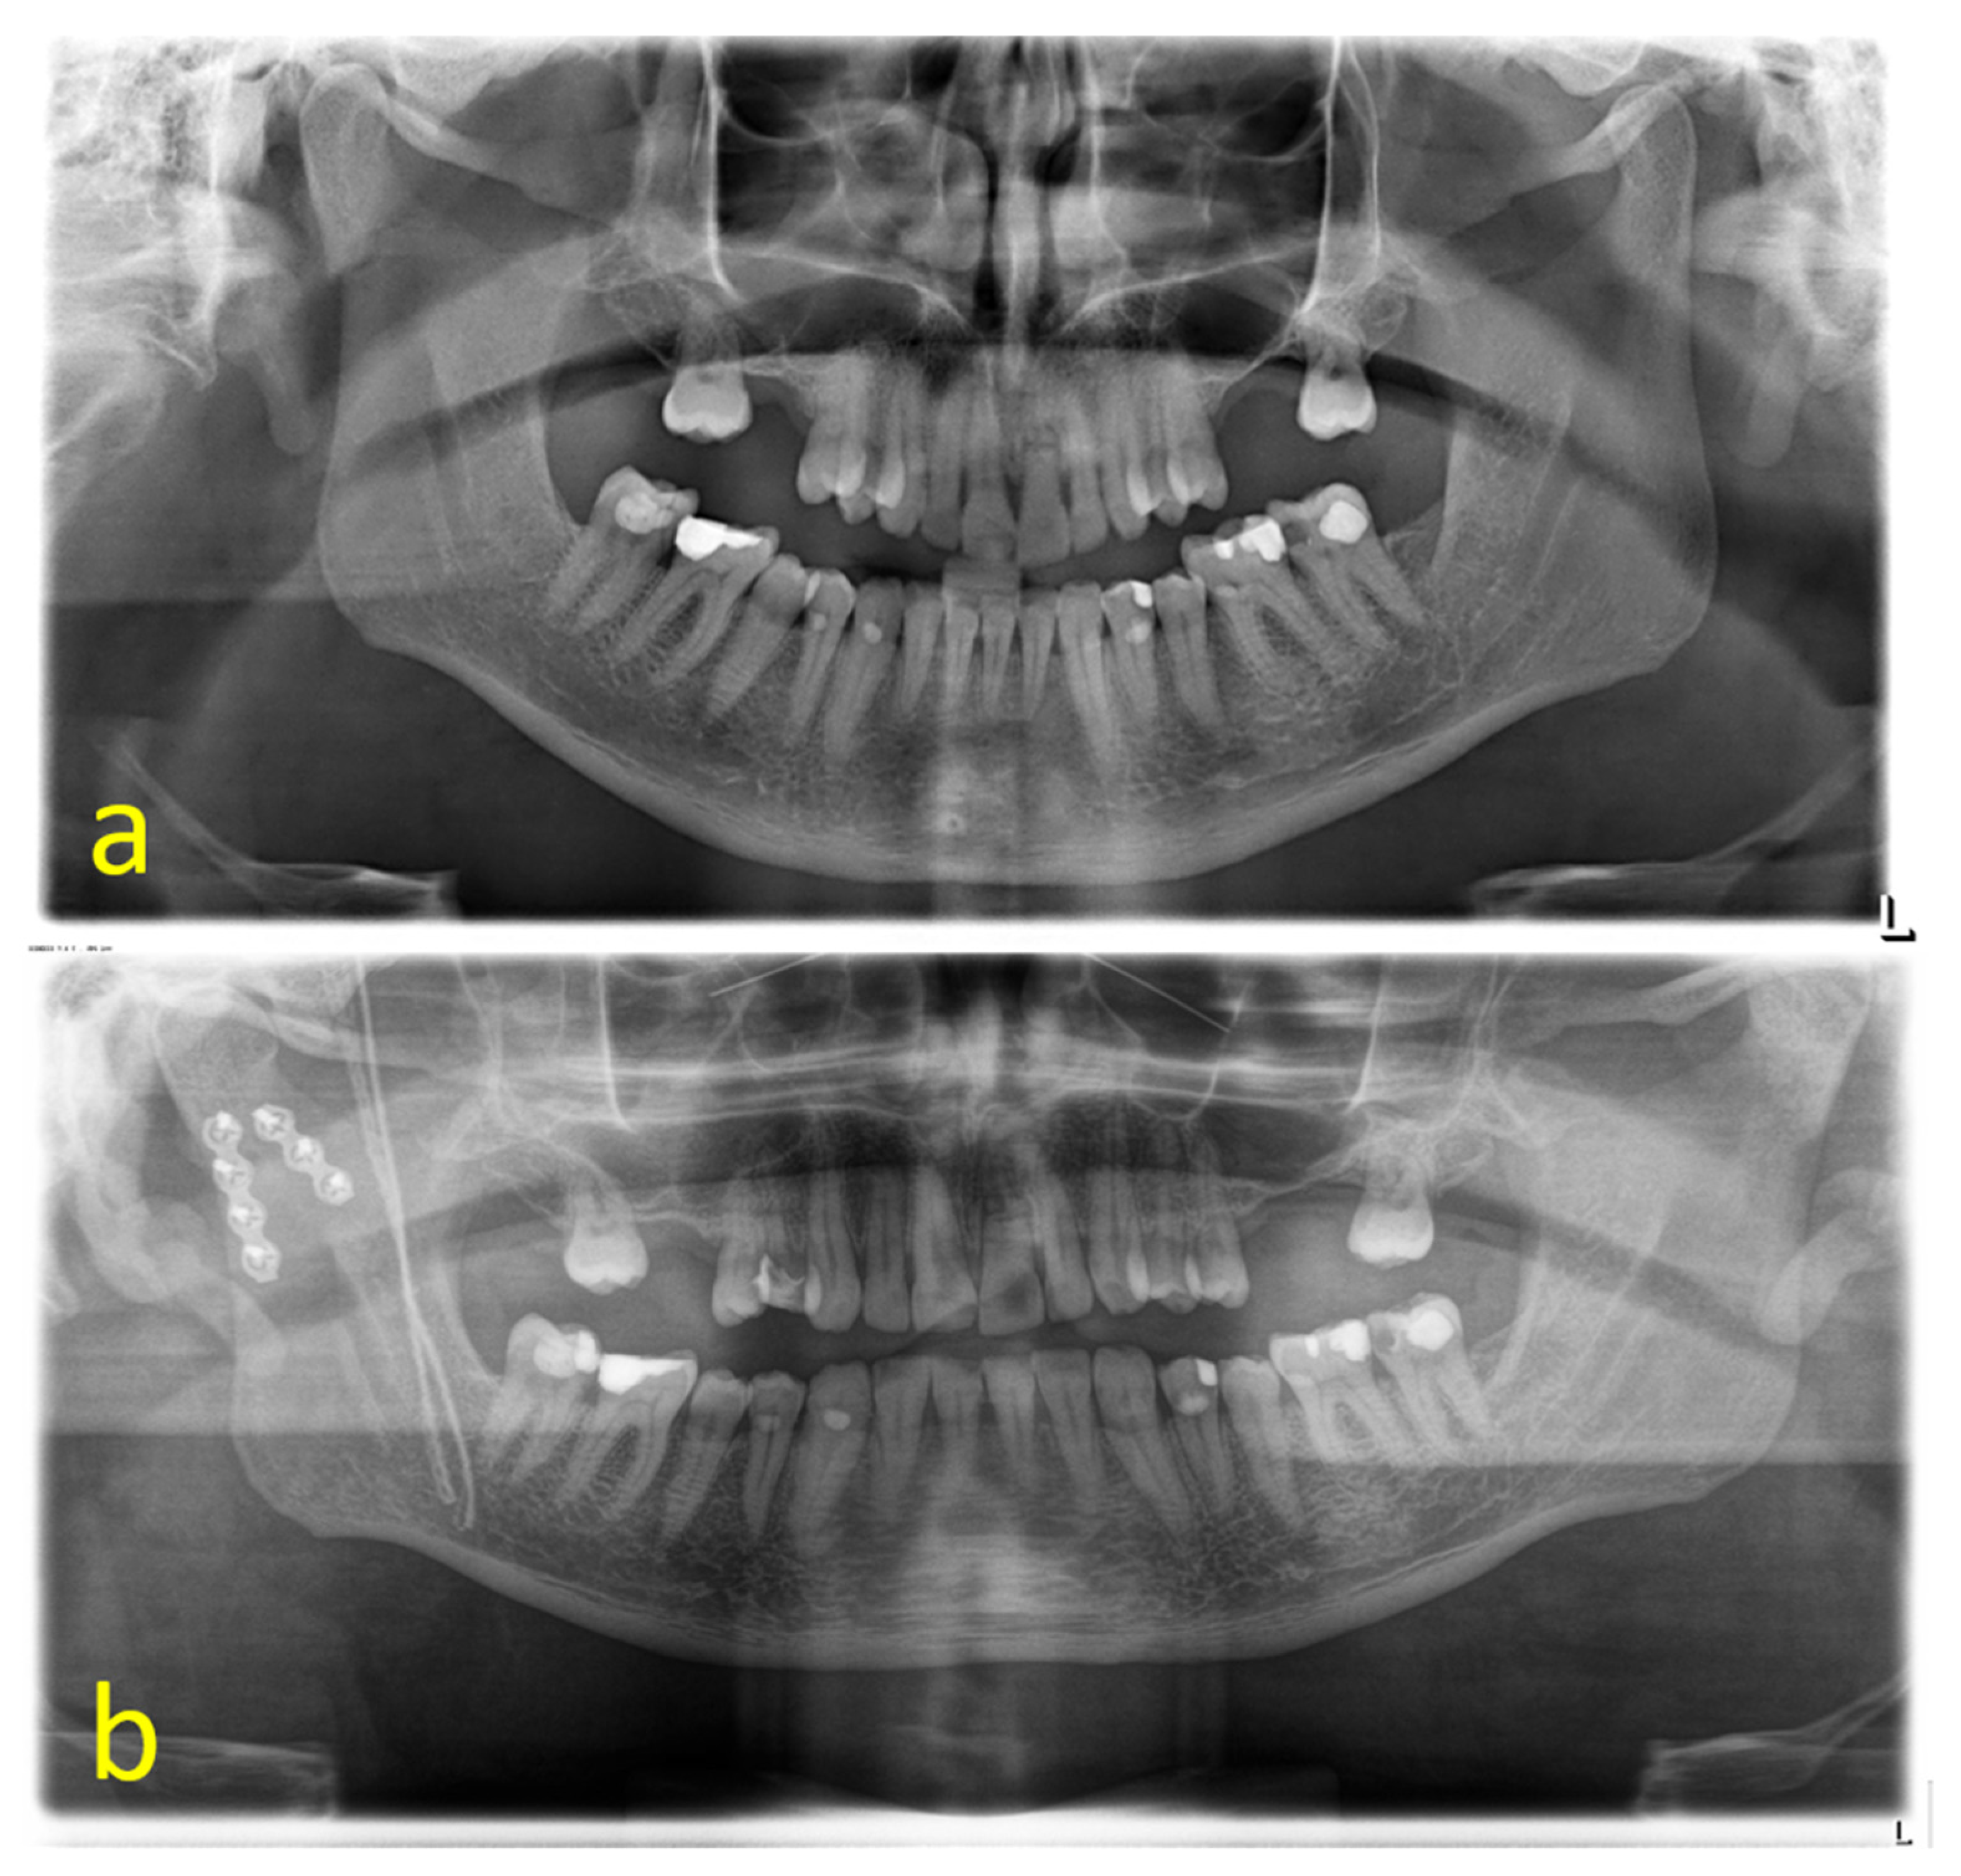

The cases could be subdivided in 62 unilateral and 53 bilateral fractures. A total of 107 of the 115 fractures were treated by ORIF (93.0%); 8 underwent conservative therapy (7.0%). Conservative treatment by intermaxillary fixation was carried out for a mean of 23.57 ± 10.37 days. According to the Spiessl and Schroll classification, the dominant type of fracture was type II (n = 61; 53.0%) (Figure 1a) followed by type III (n = 22; 19.1%), type I and V (n = 15; 13.0% each), and type IV (n = 2; 1.7%). Type I was present in 62.5% of conservatively treated fractures (n = 5), whereas 97.0% of the displaced or dislocated fractures underwent ORIF (n = 97) (Figure 1b). Type IV and V fractures exclusively received open treatment. This distribution was statistically significant (p < 0.001). A total of 15 fractures were classified as comminuted fractures by reference to preoperative 3D imaging (Figure 2a–c). A retromandibular transparotid approach was chosen in 93.5% of the open-treated cases (n = 100) (Figure 3a–f).

Figure 1. Type II fracture of the right mandibular condyle before (a) and after ORIF in double-plating technique (b) (L = left side).